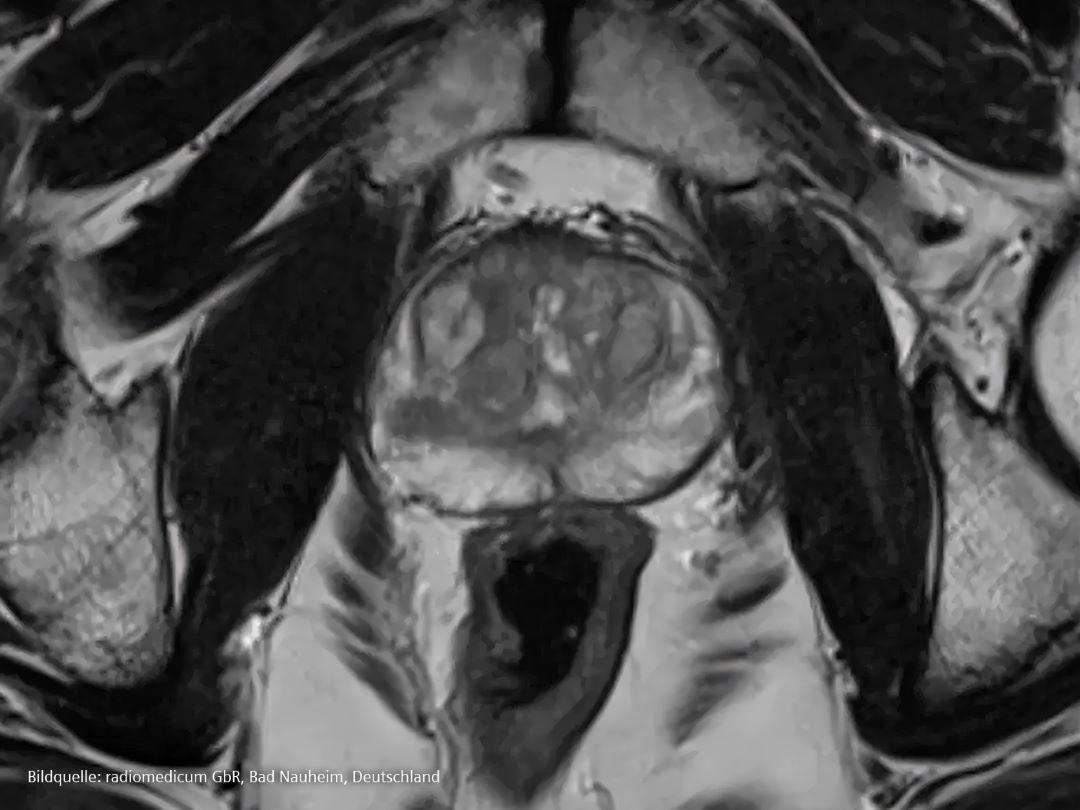

Magnetresonanztomographie

Die Magnetresonanztomographie (MRT) ist ein wichtiges Instrument bei der Behandlung von Prostatakrebs, da sie zu einer früheren Erkennung, einer präziseren Diagnose und einer auf den einzelnen Patienten zugeschnittenen Behandlung beitragen kann. Die MRT kann Weichteilgewebe und Tumore klar darstellen und ist besonders nützlich für Prostatakrebs.

Im Gegensatz zu anderen bildgebenden Verfahren werden bei der MRT Magneten verwendet, um detaillierte Bilder der Prostata und des umliegenden Gewebes zu erstellen. Die MRT gibt Ärzt*innen Aufschluss darüber, wie wahrscheinlich es ist, dass der Patient Krebs in der Prostata hat. Sie kann ihnen bei der Entscheidung helfen, ob eine Biopsie erforderlich ist und wo in der Prostata Proben entnommen werden sollten [13].

Die Magnetresonanztomographie kann zusätzliche Erkenntnisse für eine präzise Planung der Prostata-Strahlentherapie liefern. Während die Prostata das primäre Ziel der Bestrahlung ist und die volle Dosis erhalten sollte, ist sie von Organen umgeben, die empfindlich auf die Wirkung der Strahlung reagieren und so weit wie möglich geschont werden sollten. MRT-Bilder können diese Anatomie kontrastreicher darstellen und helfen dem Planer so, einen individuellen Plan zu erstellen. Im Verlauf der Behandlung können diffusionsgewichtete MRT Aufschluss darüber geben, ob die Behandlung anschlägt.

Die diffusionsgewichtete MRT verwendet spezielle Sequenzen, die die Diffusion von Wassermolekülen messen, um einen Kontrast in MR-Bildern zu erzeugen.